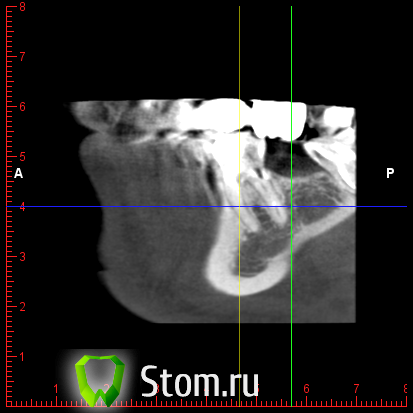

y2006 Опубликовано 3 мая, 2012 Автор Поделиться Опубликовано 3 мая, 2012 (изменено) прошу проконсультировать по поводу зуба 46. вопрос стоит в лечении и протезировании коронкой или удалении и заменой имплантом, правда ли что есть показания к удалению - перфорация корня? файлы для Romexis_Viewer по ссылке: (чуть позже)к сожалению не знаю как по другому выложить Изменено 3 мая, 2012 пользователем y2006 Ссылка на комментарий

y2006 Опубликовано 3 мая, 2012 Автор Поделиться Опубликовано 3 мая, 2012 снимок Ссылка на комментарий

y2006 Опубликовано 3 мая, 2012 Автор Поделиться Опубликовано 3 мая, 2012 (изменено) какие есть методы лечения? или есть необходимость в дополнительных проекциях? Изменено 3 мая, 2012 пользователем y2006 Ссылка на комментарий

y2006 Опубликовано 5 мая, 2012 Автор Поделиться Опубликовано 5 мая, 2012 (изменено) КТ IMAGES.rar46 зуб Изменено 5 мая, 2012 пользователем y2006 Ссылка на комментарий